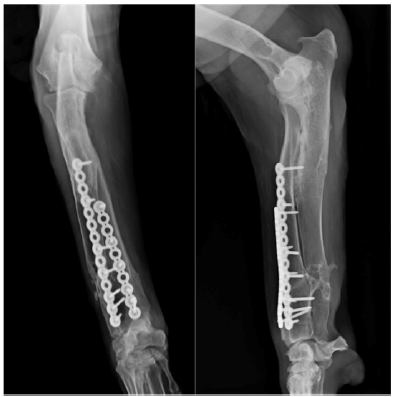

Next, a cranio medial approach to the distal radius was performed to allow the preparation of the bone for placing the device and to accomplish the ostectomy and subsequent stabilization. Once the distal shaft of the radius was exposed, the device was set in place using a press-fit mechanism (Figure 2A) and fixed to the bone with two bone forceps. The ostectomy was performed using an oscillating saw, following the cutting planes established by the guide (Figure 2B). Once the bone fragments were reduced to their preset position, 10- and 14-hole x 3.5mm locking plates were contoured and fixed to the cranial aspect of the radius. After the stabilization was complete, routine closure was performed.

Figure 2A: Surgical intervention; during surgery, the guide device was held in the predetermined point of the radius by mean of a press-fit system.

Figure 2B: Oscillating saw was used to cut the bone using the guide device (B), and finally both fragments were reduced and stabilized as in the “in vitro” surgery.

Follow-up radiographs (Figure 2C) were performed at 4, 8, 12, 16and 24weeks post-surgery, at which point no anomalies in bone healing were detected. Orthopedic examination revealed immediate correct alignment and normal weight bearing of the limb, with the resolution of lameness 16 weeks post-operatively. Three years postoperatively, an orthopedic exam and radiography were performed (Figure 2D). This revealed the satisfactory resolution of clinical signs with no lameness. At this time, elbow range of motion was normal. A minor reduction in carpal range of motion was detected but was non-painful.